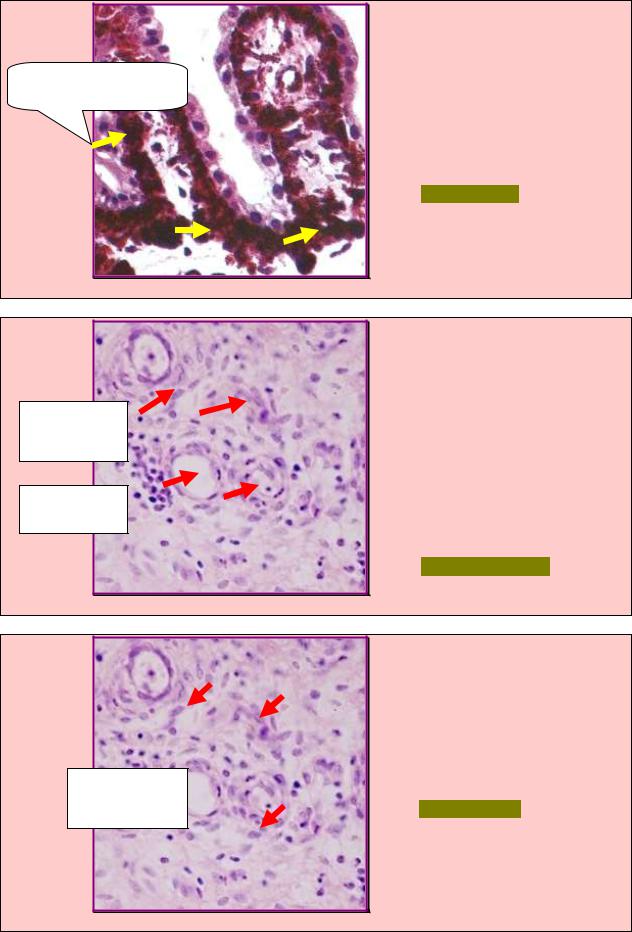

ЗАДАНИЕ 4.105 |

В препарате |

эпидермиса кожи |

Поглощение и отражение |

выявили |

меланинсодержащие |

клетки (стрелки), специфи- |

ультрафиолетовых лучей |

ческая |

функция |

которых |

представлена |

на |

рис.4.105. |

Назовите данные клетки. |

А. Ретикулярные. |

Б. Интердигитирующие. |

В. Пигментные. |

Г. Макрофаги. |

Д. Дендритные. |

Рис. 4.105 |

ЗАДАНИЕ 4.106 |

В |

препарате |

раны |

кожи |

новообразованную |

соединительнотканную |

ткань, |

Секреторно |

морфологические |

признаки |

активные |

которой |

представлены |

фибробласты |

рис.4.106. |

Назовите |

данную |

ткань. |

Кровеносные |

А. Ретикулярная. |

Б. Пигментная. |

сосуды |

В. Жировая. |

Г.Слизистая. |

Д. Грануляционная. |

Рис. 4.106 |

ЗАДАНИЕ 4.107 |

выявили соединительную ткань |

обозначенную |

рис.4.107, |

образование |

обеспе- |

чивают |

клетки |

(стрелки). |

Грануляционная |

А. Макрофаги. |

ткань |

Б. Фибробласты. |

В. Лейкоциты. |

Г. Эндотелиоциты. |

Д. Адипоциты. |

Рис. 4.107 |